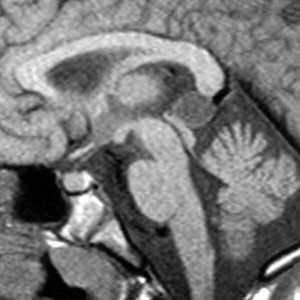

Коллоидная киста - это врождённое нейроэпителиальное образование. Коллоидная киста выстлана эпителием и имеет фиброзную капсулу. Она составляют около 1-2% объемных внутричерепных образований. Обычно диагностируются в возрасте между 30 и 50 годами. При МРТ головного мозга видно, что киста всегда расположена в переднее-верхнем отрезке III желудочка между отверстиями Монро. Контур ее четкий, форма округлая, содержимое бывает неоднородное. Размер от 3 мм до 4 см, при больших размерах она закрывает отверстия Монро и вызывает окклюзионную гидроцефалию. Сигнал зависти от примеси белка к ликвору. При наличии белкового мукоидного содержимого киста гиперинтенсивна на Т1-взвешенных МРТ и гипоинтенсивна на Т2-взвешенных МРТ, но встречаются варианты гиперинтенсивные на томограммах обоих типов кольцевидные или смешанные . Контрастирования не наблюдается.

КТ и МРТ головного мозга. Коллоидная киста III желудочка.

Киста кармана Ратке представляет собой редко встречающееся образование из остатков эмбриональной эктодермы (щель Ратке), расположенное между долями гипофиза. Выявляется в любом возрасте, но чаще в 50-60 лет. Клинические проявления связаны с масс-эффектом. При головного мозга выявляется небольшая (3-5 мм) киста с четким контуром, без отека вокруг, однородная по структуре. Сигнал зависит от содержимого. При серозном содержимом сигнал типично жидкостный, при мукоидном киста светлая на Т1-взвешенных МРТ. В редких случаях киста достигает больших размеров и даже выходит за пределы седла. Стенка кисты иногда усиливается при контрастировании.

МРТ головного мозга. Т2-взвешенная корональная МРТ. Киста кармана Ратке.